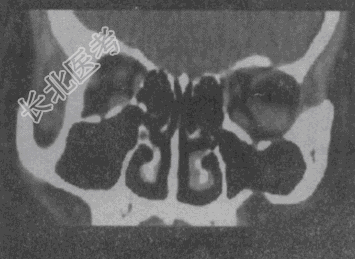

- 单项选择题女,52岁, 左眼球突出20余年,T

均正常, 影像检查如图所示,最可能的诊断是